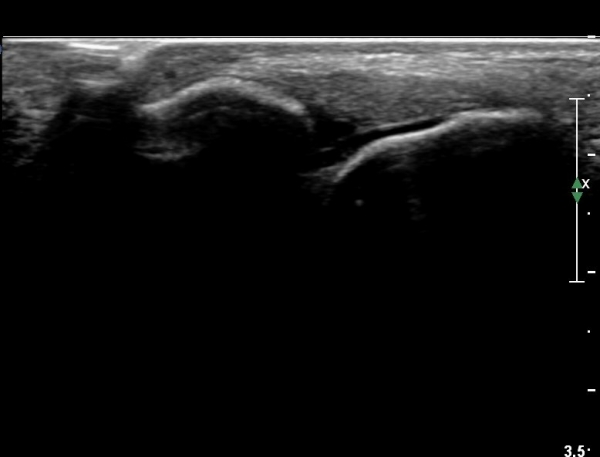

¹ß¸ñ À§¿¡¼­ ¸»´Ü ¾ÕÂÊ °æ°ñºñ°ñÀδë Á¾´Ü¸é°Ë»ç¿¡¼­ ƯÀÌ ¼Ò°ßÀ» º¸ÀÌÁö ¾Ê´Â´Ù(»çÁø 2, 3).